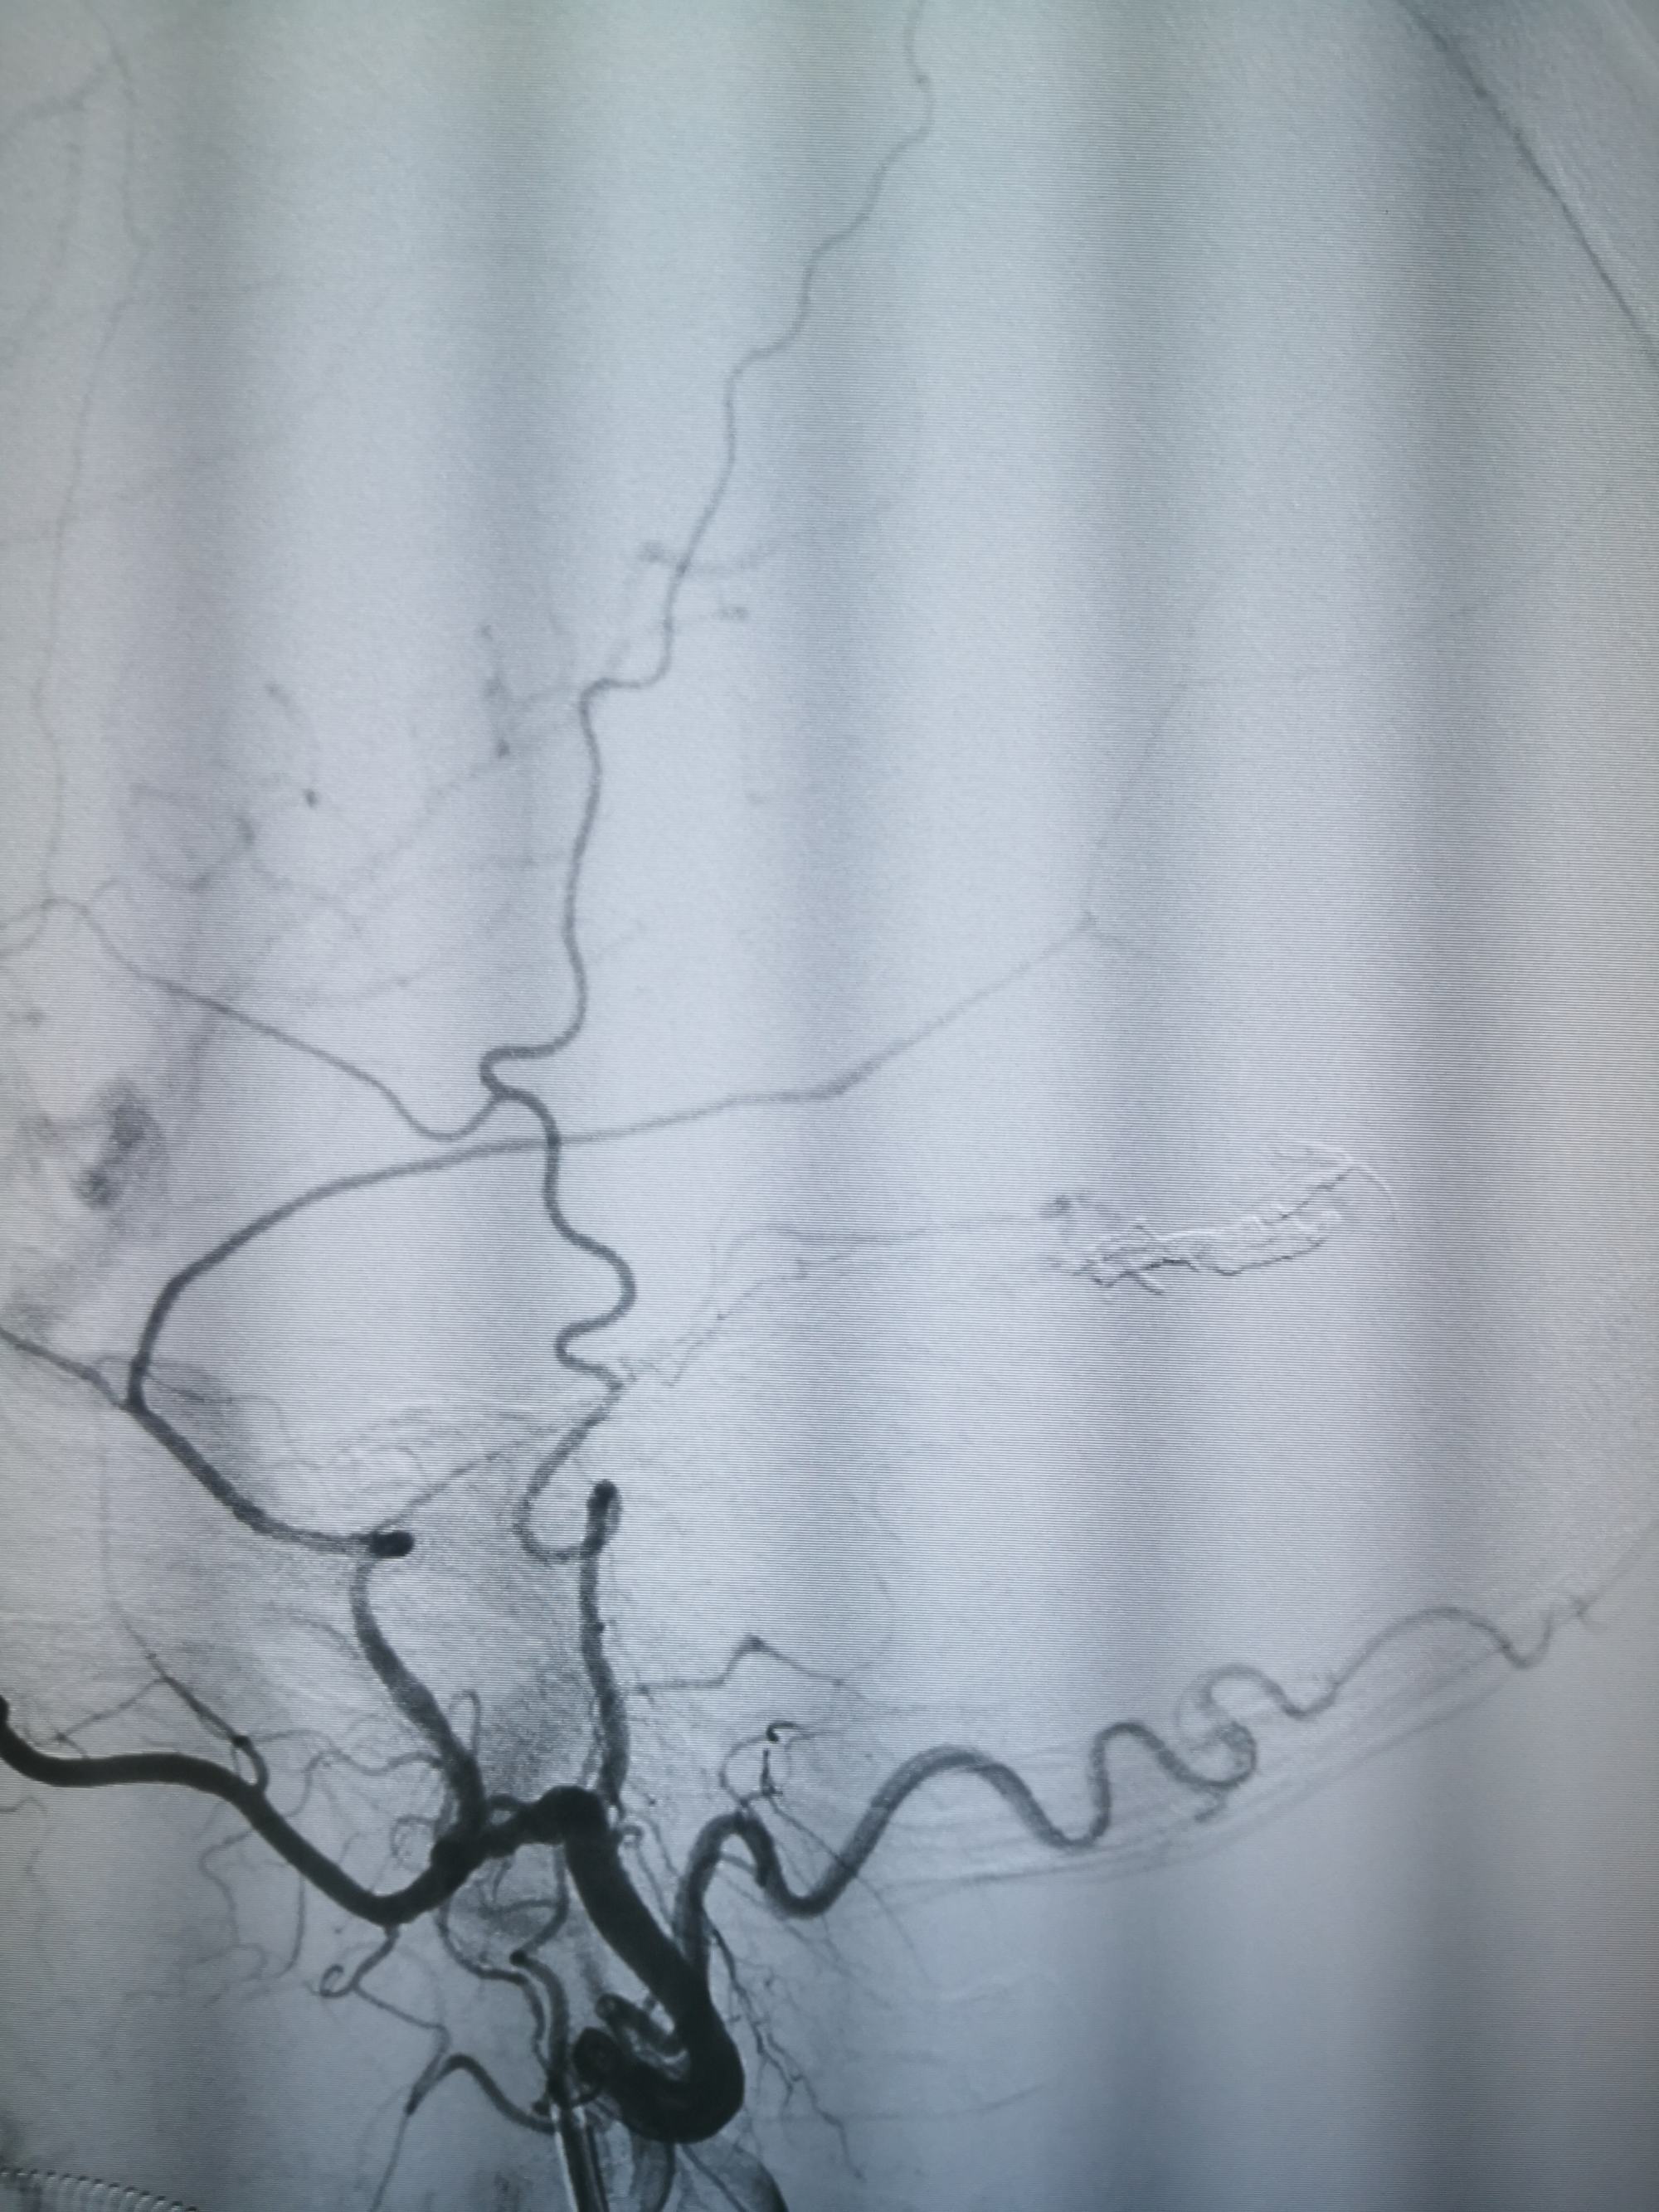

微导管到达瘘口,打胶

微导管到达瘘口,打胶